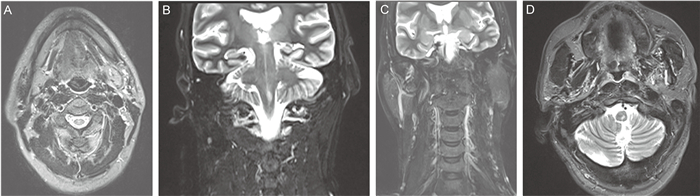

入院时查体生命体征平稳,神清,皮肤苍白,巩膜无明显黄染,无皮疹及出血点,无肝掌及蜘蛛痣;双肺呼吸音粗,未闻及干湿啰音;心脏听诊无异常;腹软,全腹无明显压痛、无反跳痛,肝脾肋下未触及,移动性浊音阴性,肠鸣音正常,双下肢无水肿。入院查白细胞指标值正常,血红蛋白84 g/L,C反应蛋白(C-reactive protein,CRP)15.9 mg/L,降钙素原正常,肝功能正常,肿瘤标志物全套均正常,乳酸脱氢酶正常,血清β2微球蛋白4.6 mg/L。人类免疫缺陷病毒(human immunodeficiency virus, HIV)抗体阴性。胸部及全腹部计算机断层扫描(computed tomography,CT)提示肺下叶背侧坠积性炎性改变,双侧胸膜增厚粘连;胃壁增厚;纵隔、双侧腋窝、腹膜后及肠系膜走行区淋巴结增多、肿大,较大者2.0 cm,不排除转移性病变;双侧肾上腺明显增粗,不排除转移性病变;腹盆腔积液(见图 1)。

A: Increased and enlarged lymph nodes in neck in CT scanning. B: Increased and enlarged lymph nodes in axilla in CT scanning. C: Increased and enlarged lymph nodes in mediastinum in CT scanning. D: Bilateral adrenal gland thickening and increased and enlarged lymph nodes in mediastinum in CT scanning. 图 1 胸部及全腹部CT检查结果(2021年4月) Fig. 1 CT examination results of chest and abdominal (April 2021) |

2.3 影像特征马尔尼菲篮状菌病累及呼吸系统时常见的胸部CT征象为结节、磨玻璃影,斑片浸润或肺实变等一系列类似肺结核的表现,部分患者可见弥漫性粟粒样影,常同时合并纵隔及肺门淋巴结肿大和胸腔积液[27-28]。腹腔感染的CT表现有淋巴结肿大、腹腔积液、肝脾肿大,其中腹膜后及肠系膜淋巴结肿大较为常见,腹腔干旁和肠系膜区淋巴结肿大最为常见,且肿大程度更为明显[29]。MRI检查可见沿肠系膜血管边缘分布的多发淋巴结肿大伴环形强化,淋巴结之间一般界限清晰。马尔尼菲篮状菌病累及骨骼时,影像学表现有虫蛀样骨质破坏、骨膜增生等,甚至可出现骨折[30]。发射型计算机断层显像(emission CT, ECT)检查可见骨骼放射性摄取增加[31]。正电子发射计算机断层显像(Positron emission tomography-CT, PET-CT)检查可显示全身弥漫性淋巴结肿大、多处骨代谢活跃和骨质破坏[32]。

本例患者CT检查见颈部、纵隔、腹膜后及肠系膜淋巴结肿大,双侧肾上腺明显增粗,腹腔积液,均考虑为马尔尼菲篮状菌感染表现,另外延髓左侧出现的异常信号,喉镜下双侧圆枕覆盖白色伪膜样新生物,左侧咽侧壁、舌根部隆起,左侧声带后上方见囊肿样物,考虑为该病原累及中枢神经系统及上呼吸道的表现。患者经抗真菌治疗后,咽痛好转,痰液分泌减少,左侧眼睑不能睁开、左侧眼球活动受限、轻度吐词不清、口角歪斜等情况逐渐好转,经影像学复查肿大的淋巴结消失,肾上腺正常,延髓病变明显缩小。